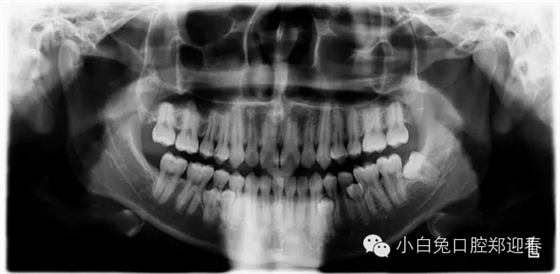

多生牙

額外牙可發(fā)生于乳牙列,也可發(fā)生于恒牙列,但恒牙列發(fā)生率多于乳牙列。額外牙經常在上頜出現,上、下頜出現比例為10∶1,可單個或多個、單側或雙側出現,形態(tài)可同正常牙,也可是畸形牙、過小牙。

額外牙最常發(fā)生的位置在上中切牙之間,稱之為正中牙。其次是上頜磨牙區(qū),為上頜第四磨牙,位于第三磨牙遠中,很少萌出口腔,常從照片發(fā)現。有時也可在下頜、上頜前磨牙區(qū)、上頜側切牙區(qū)。

多生牙病例集錦